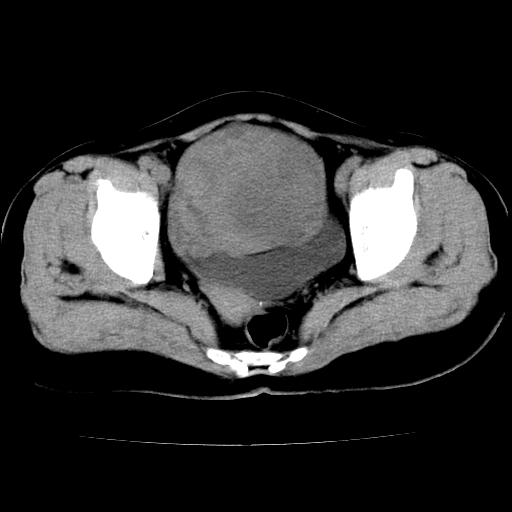

标题: CT24785:女,62岁,发现下腹部肿物半年。 [打印本页]

女,62岁,发现下腹部肿物半年,下腹部不适。

老年女性患者,盆腔囊实性占位,ct增强不均匀强化,未见壁结节,未见腹水及盆腔积液,考虑附件囊腺瘤可能性大!

考虑子宫平滑肌肉瘤可能性大。

卵巢囊腺瘤或囊腺癌可能。

子宫平滑肌瘤